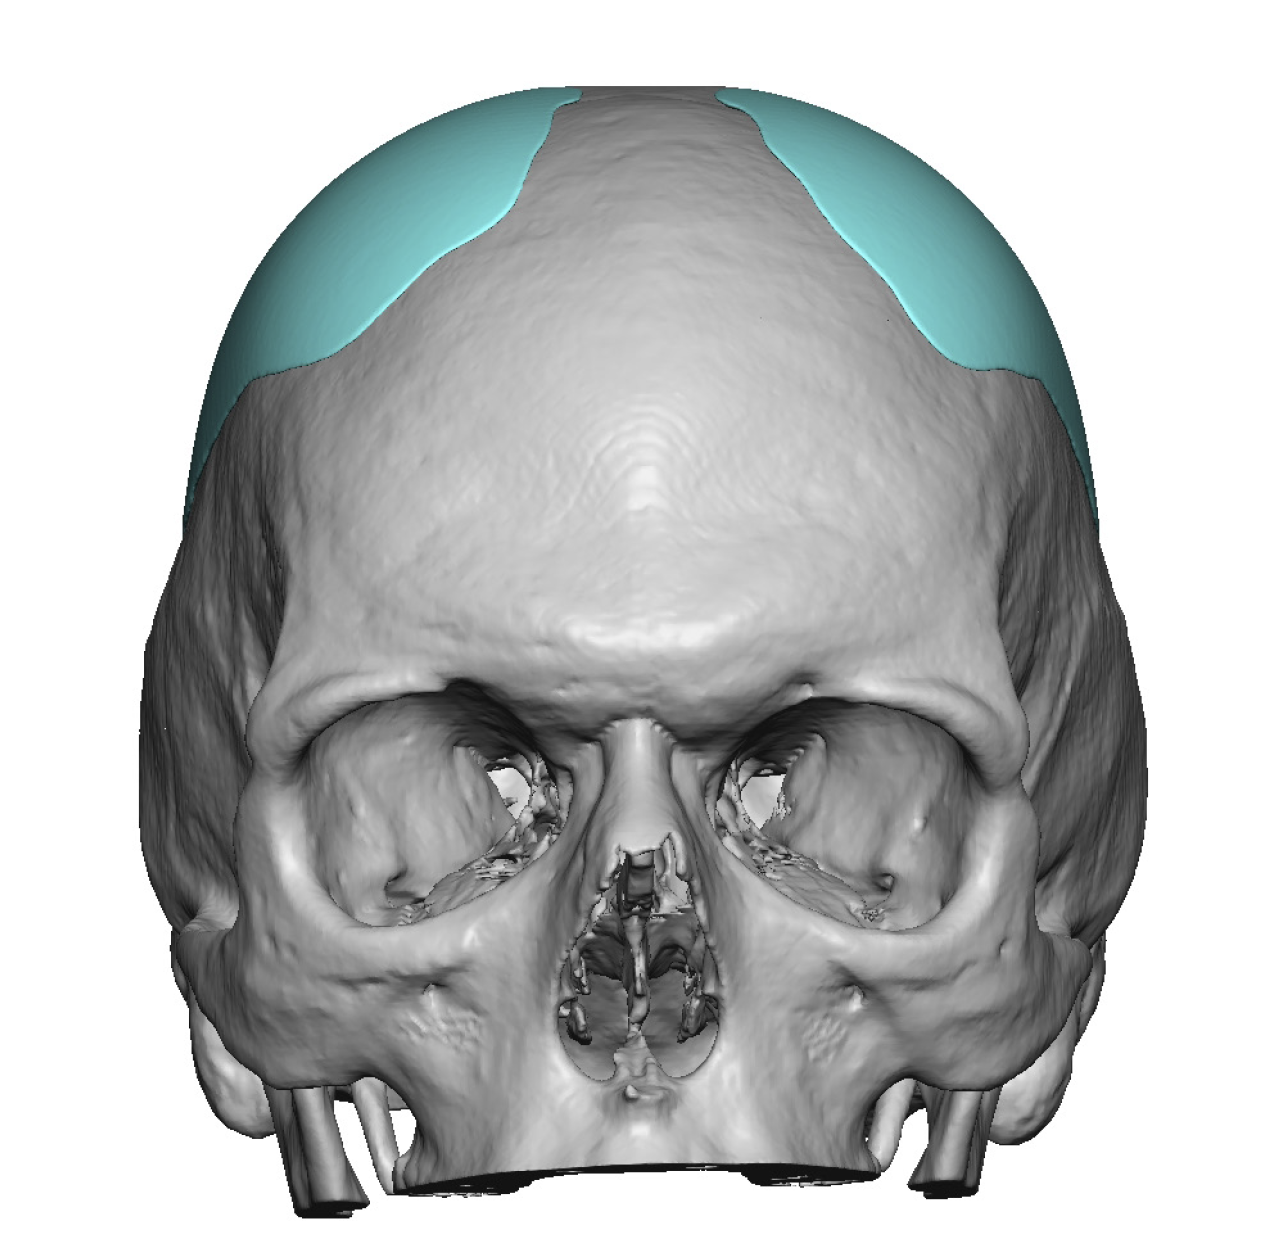

Patient 28

Desire for rounder shape to the top of the head from a congenital parasagittal deficiency skull shape.

Custom skull implant designed to fill in the parasagittal deficiencies.

Desire for rounder shape to the top of the head from a congenital parasagittal deficiency skull shape.

Custom skull implant designed to fill in the parasagittal deficiencies.